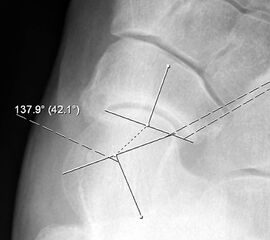

Talo-calcanearer Winkel (Abb. 6 e)

Auf der seitlichen, stehenden Aufnahme des Fußes wird ebenfalls der laterale Talo-Metatarsale I Winkel (Abb. 6 d) gemessen und so das kollabierte mediale Längsgewölbe dokumentiert. Auch hier gilt ein Talo-Metatarsale I Winkel von > 5° (nach plantar konvex) als pathologisch 21. Der Kollaps findet dabei meist im Talonaviculargelenk, seltener in der Naviculocuneiform-Gelenkreihe statt. Instabilität und Arthrose im 1. TMT sollten ausgeschlossen oder bei der Operationsplanung mit einbezogen werden. Weitere wichtige radiologische Messungen zur Beurteilung der Planovalgus-Statik und Progression der Deformität sind der laterale talo-calcaneare Winkel (Abb. 6 e) und der Abstand des Os cuneiforme-Unterrandes zum Untergrund (Abb. 6 f, Cuneiform height, 22. Eine anteriore Translation des Talus auf dem Kalkaneus findet man sowohl auf der ap, als auch auf der seitlichen Aufnahme des Fuβes mit Aufhebung der Cima-Linie.